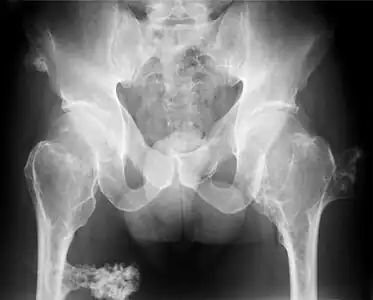

Hereditary multiple osteochondromas (HMO), also known as hereditary multiple exostoses, is a disorder characterized by the development of multiple benign osteocartilaginous masses (exostoses) in relation to the ends of long bones of the lower limbs such as the femurs and tibias and of the upper limbs such as the humeri and forearm bones. They are also known as osteochondromas. Additional sites of occurrence include on flat bones such as the pelvic bone and scapula. The distribution and number of these exostoses show a wide diversity among affected individuals. Exostoses usually present during childhood. The vast majority of affected individuals become clinically manifest by the time they reach adolescence.[1][2] A small percentage of affected individuals are at risk for development of malignant transformation namely sarcomas. The incidence of hereditary multiple exostoses is around 1 in 50,000 individuals.[3] Hereditary multiple osteochondromas is the preferred term used by the World Health Organization.

It is characterized by the growth of cartilage-capped benign bone tumours around areas of active bone growth, particularly the metaphysis of the long bones. Typically five or six exostoses are found in upper and lower limbs. Most common locations are:[15]

HME can lead to the shortening and bowing of bones; affected individuals often have a short stature. Depending on their location the exostoses can cause the following problems: pain or numbness from nerve compression, vascular compromise, inequality of limb length, irritation of tendon and muscle, Madelung's deformity[16] as well as a limited range of motion at the joints upon which they encroach. A person with HME has an increased risk of developing a rare form of bone cancer called chondrosarcoma as an adult.[16] Problems may be had in later life and these could include weak bones and nerve damage.[17][18][19] The reported rate of transformation ranges from as low as 0.57%[12] to as high as 8.3% of people with HME.[20] Some authors have described an association between HME and the presence of popliteal pseudoaneurysms [21]